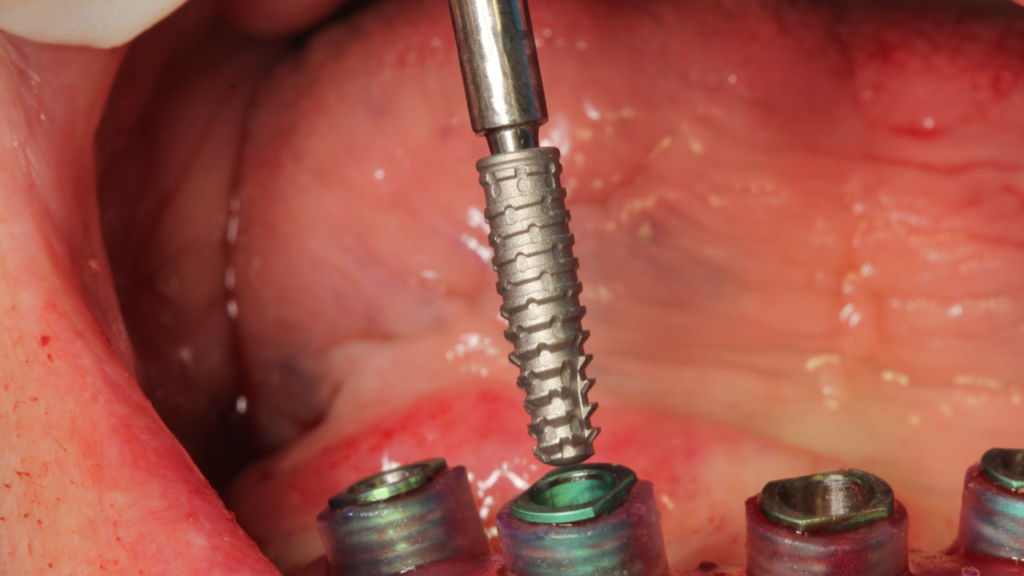

Através da imagem do osso recortado é planejada a guia de perfuração que vai se encaixar de uma maneira perfeita no osso recortado.

O planejamento acima, foi feito para a instalação de uma prótese fixa aparafusada final, com estrutura metálica rígida e acrilização, no mesmo dia da cirurgia. A regularização do rebordo da paciente permitiu a instalação dos implantes em um posicionamento 3D ideal para uma reabilitação protética com os parâmetros biomecânicos, funcionais e estéticos adequados, transformando uma situação com várias limitações e dificuldades em um caso favorável, de uma maneira simples e previsível.